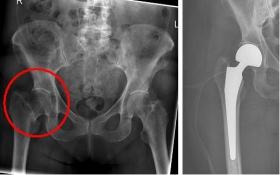

In older age and with stronger displacement of the fracture can be done by a duo-head prosthesis. Here only the femoral head is replaced, the hip socket is preserved. In case of simultaneous hip arthrosis, a total endoprosthesis (hip replacement) with replacement of the acetabular cup can be used.

Picture: This picture shows the treatment of a severely displaced fracture with a so-called duo head prosthesis. The acetabulum was left here.

Picture: In this case, there was already a wear of the hip joint and the affected patient was relatively young, so that a cement-free total endoprosthesis (TEP) of the hip was selected for the treatment of the femoral neck fracture. Here, in addition to the femoral head, the acetabular cup was replaced by an implant.